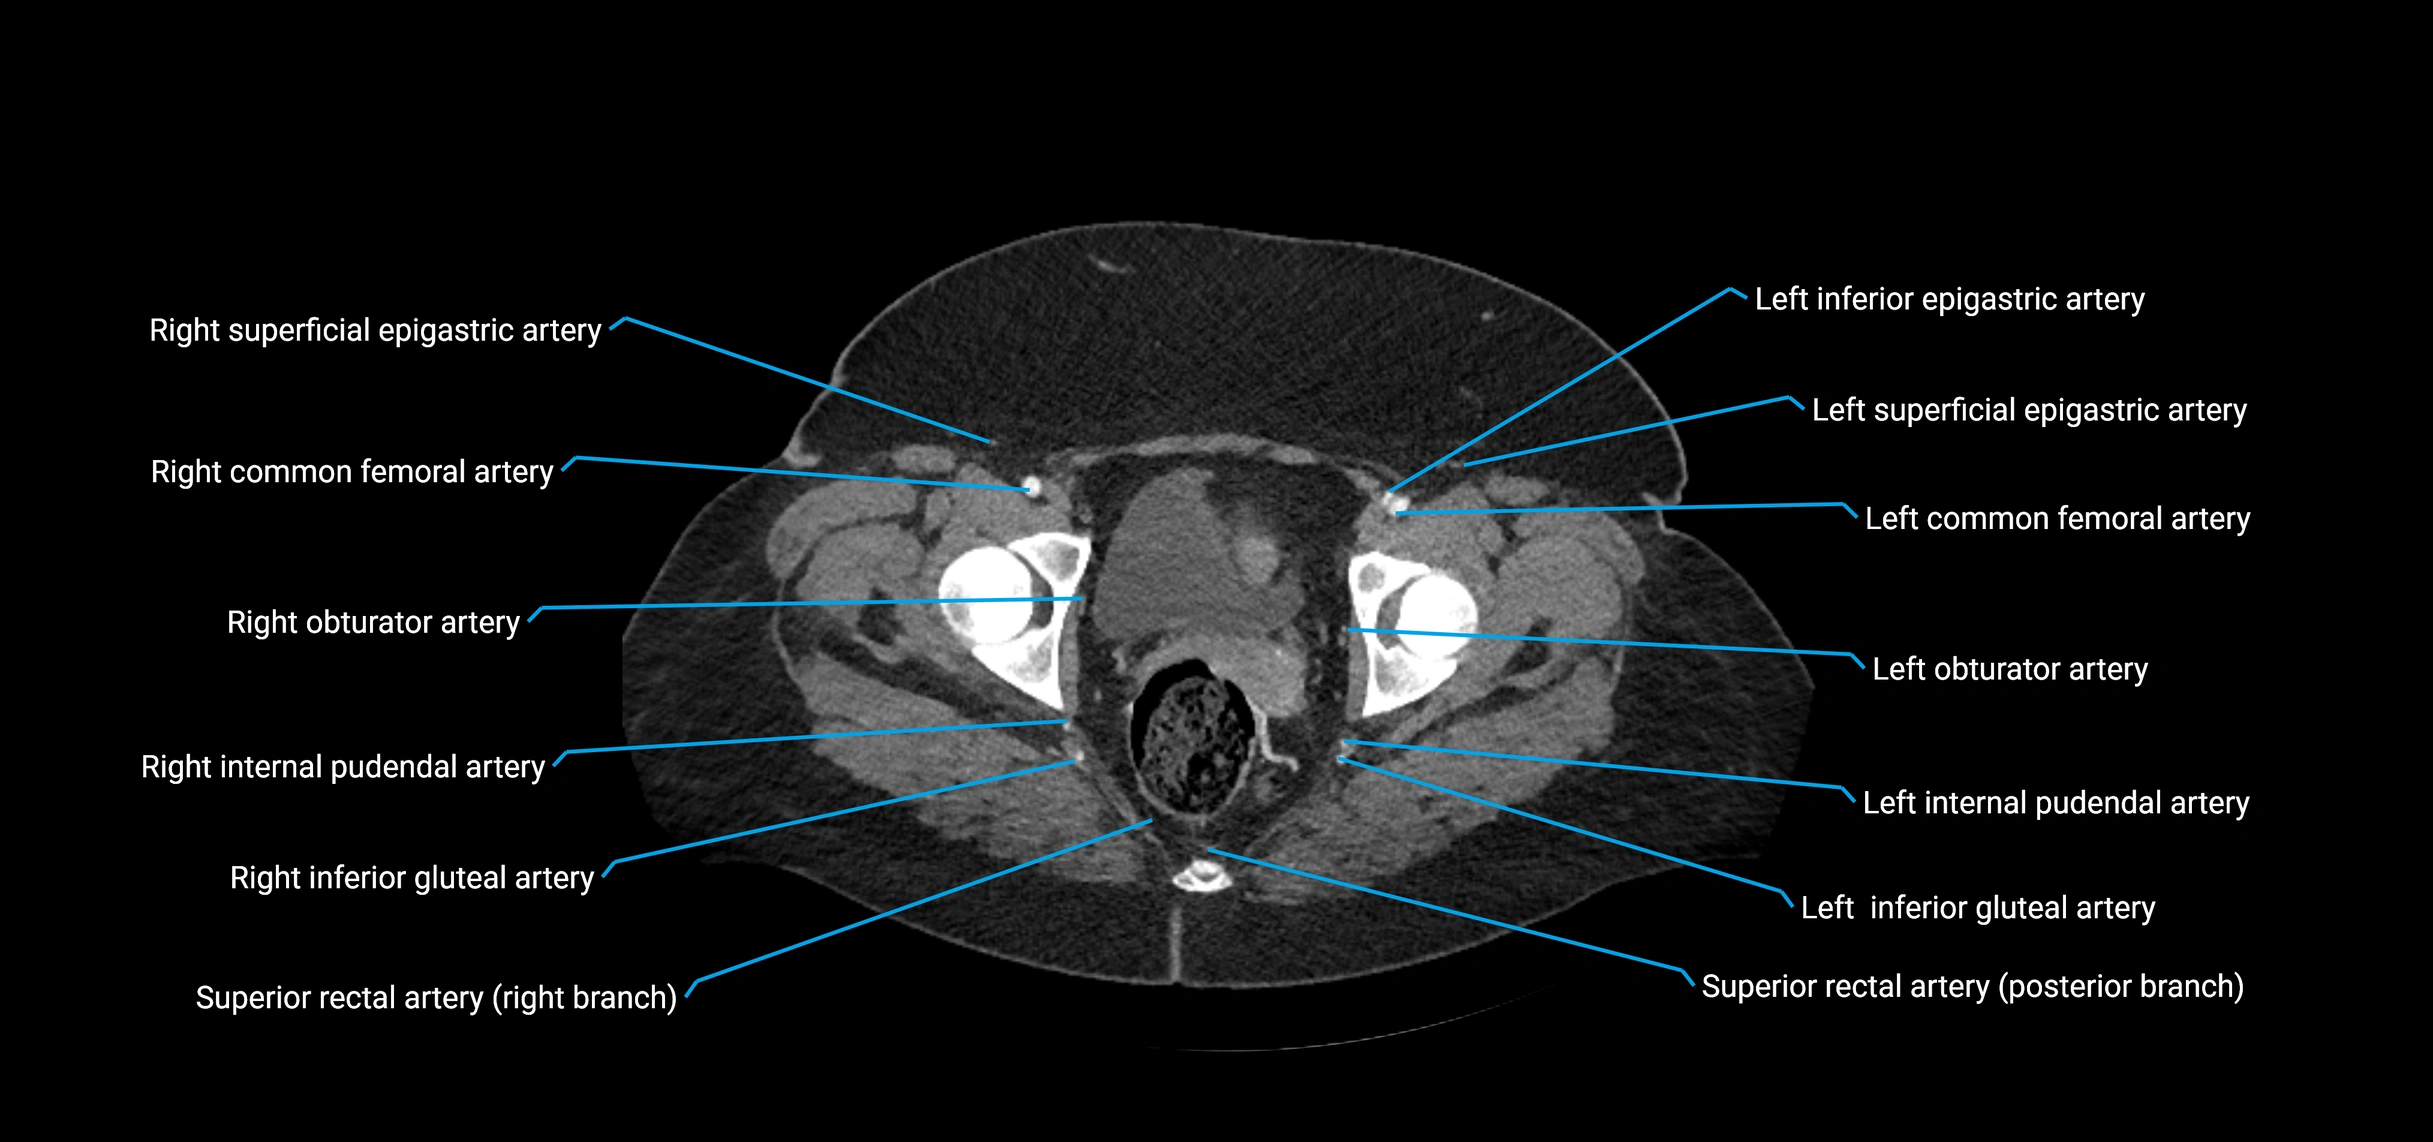

Contrast-enhanced CT (CTA):

• Gold standard for abdominal aortic imaging

• Provides excellent detail of lumen, wall, aneurysm, thrombus, and branch vessels

• Multiplanar and 3D reconstructions help in aneurysm measurement, stent graft planning, and dissection evaluation

• Detects acute rupture, traumatic injury, or occlusion with high sensitivity